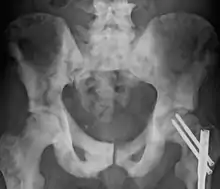

Sclerosis of the bones of the pelvis due to prostate cancer metastases | |